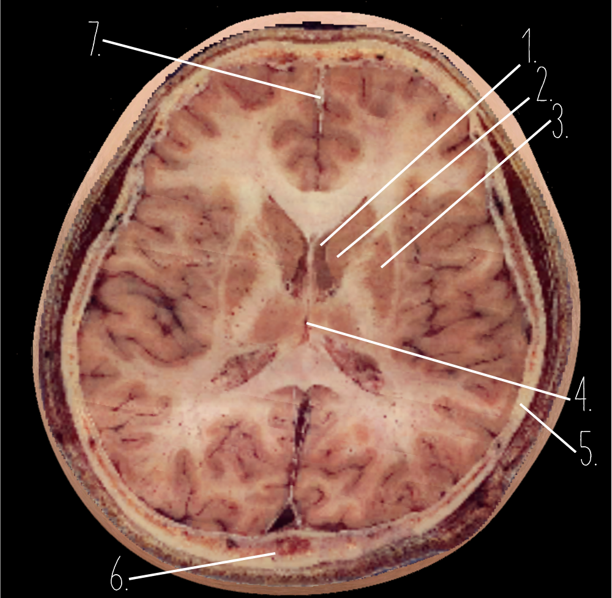

Brain Cross Sectional

1?

Choroid Plexus

2?

Lateral Ventricle

3?

Caudate Nucleus

4?

Third Ventricle

5?

Parietal Bone

6?

Occipital Bone

7?

Falx Cerebri